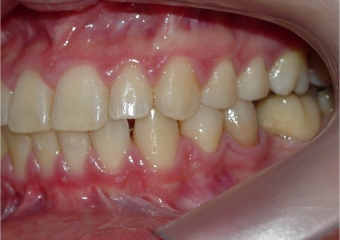

Mordida perfil final